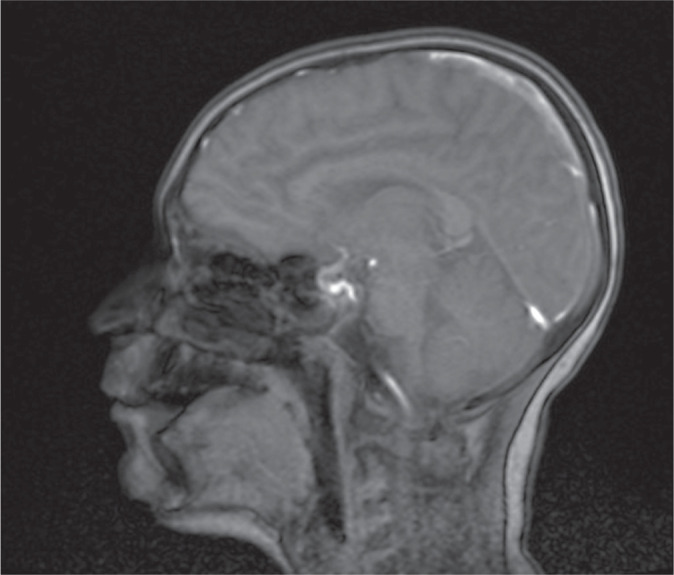

Hypoglycemic encephalopathy (HE) is a type of encephalopathy resulting from extremely low blood glucose level. Symptoms are not specific and can be misdiagnosed very often. It can occur during deep and/or prolonged hypoglycemia, which may be a result of inadequately controlled diabetes. Here, we report a case of an 11-year old male patient diagnosed with type 1 diabetes mellitus treated with the use of insulin pump who was admitted to the Pediatric Neurology Department because of multiple incidents of seizures. Boy was found unconscious by his mother. The blood glucose level on the glucometer was 35 mg/dl. It turned out that the reason of hypoglycemia was inadequate insulin dosing. He was given intravenous glucose by the ambulance service without improvement in the state of consciousness. Brain MRI revealed in both cerebral hemispheres, symmetrically, elevated white matter signal, mainly in the subcortex and cortex of the frontal and occipital and parietal lobes with features of diffusion restriction. EEG revealed generalized slow brain activity, without obvious epileptiform. Boy was provided with a variety of antiepileptic drugs. Unfortunately, none of them yielded with satisfactory results so far and the patient is still suffering from drug-resistant epilepsy. In conclusion, glucose is one of the key metabolic agents for the proper brain function and any imbalances in its blood level may impair the neuronal computation. Thus, it is extremely important, especially among diabetic patients, to control glucose blood level and avoid any disturbances, as they may lead to severe consequences, such as HE and drug-resistant epilepsy.